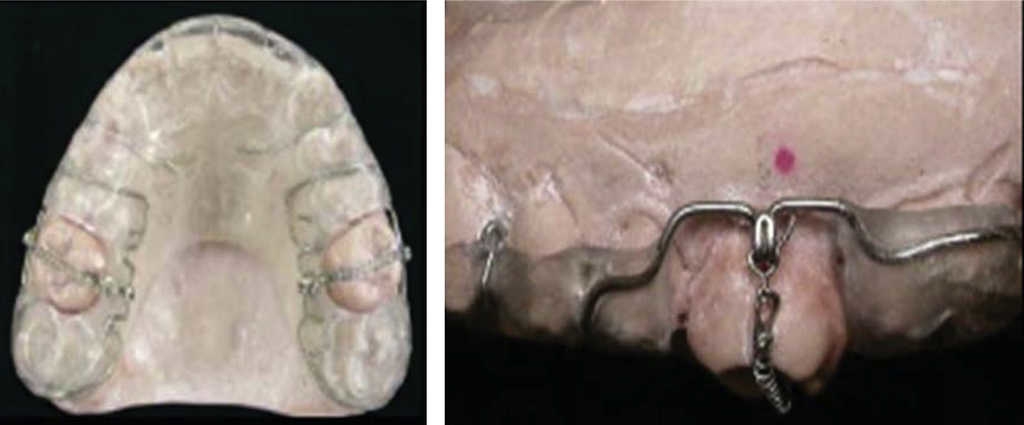

In 2010, Oliveira published an article where he described a combination of alveolar corticotomy with a modified maxillary splint with nickel-titanium spring. The aim of this technique was to intrude over-erupted molars (Figure 16).7

Oliveira reported that in one patient, 4 mm intrusion was achieved in 2.5 months, and in another patient, 3 to 4 mm intrusion was accomplished in 4 months.7 This technique is used in adult or young patients with healthy or reduced periodontium; it facilitates bi-maxillary protrusion correction, closure of skeletal open bite, intrusion of molar with removable appliances and treatment of patients with cleft lip and palate.

In the surgical technique, a full-thickness flap is raised from a vestibular, palatal or lingual approach, on the area where dental movement is to be conducted. After this, vertical corticotomies are performed with a round 701 burr in inter-radicular spaces 2 mm away from the alveolar crest and surpassing by 2 or 3 mm dental apexes, care must be exerted to barely touch medullar bone. At this height, horizontal corticotomies are performed to link vertical corticotomies (Figure 17).

Figure 17 Corticotomy executed in the molar to be intruded, to later place a nickel-titanium spring..

Once the aforementioned is completed, the flap is repositioned and sutured, placed on a modified acrylic splint, and leaving uncovered the occlusal aspect of the molar to be intruded. Seven days later orthodontic forces are applied, and after this, forces are applied every 14 days until desired intrusion is achieved (Figure 18).7

Figure 18 Inter-consultation with orthodontics specialist from beginning of treatment until achieving molar intrusion..

Advantages of this technique are the following: it facilitates difficult orthodontic movements, allows for significant transversal and anterior-posterior dental expansion, corrects moderate to severe skeletal malocclusions, and provides clinical results twice or three times faster when compared to conventional orthodontic treatment.7